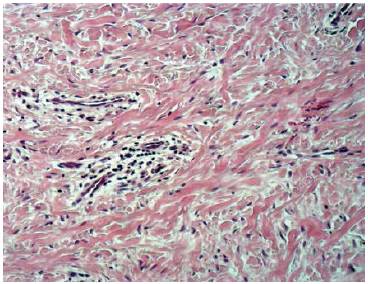

En la figura 6 se observa el conjuntivo con abundantes fibras colágenas desordenadas, algunos capilares, y algunas zonas de infiltrado inflamatorio en la zona superior.

En la figura 7 se observan fibroblastos, sus núcleos y fibras dispuestas en distintas direcciones. También se identifican vasos sanguíneos y algunos linfocitos.

Teniendo esta información en cuenta el diagnóstico histopatológico resulta en granuloma piógeno fibrosado.